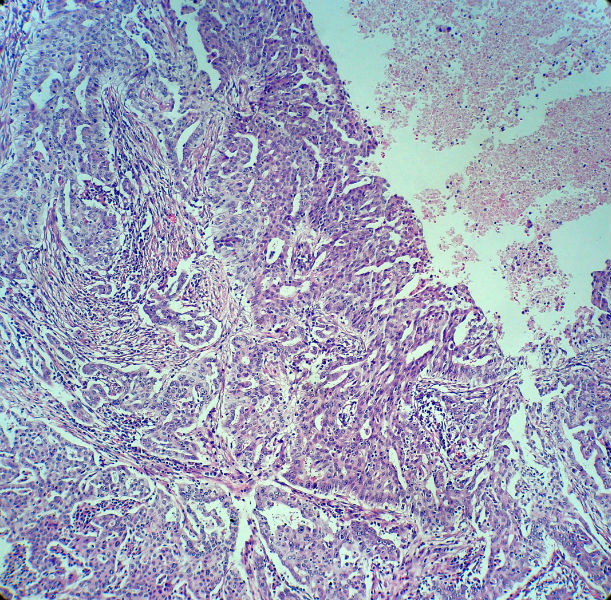

男,82岁,小肠穿孔紧急手术。

大体,小肠一段,长约60厘米,与粘膜面可见三个溃疡型肿物,肠系膜淋巴结肿大。

肿瘤呈巢片状分布,细胞大小相对一致,胞浆丰富,胞核呈细颗粒状,可见小核仁,血管较丰富,考虑神经内分泌肿瘤,加做免疫组化(Ki67、Syn、NSE、CgA、CD56)分级。

腺癌,部分为神经内分泌癌

神经内分泌癌。